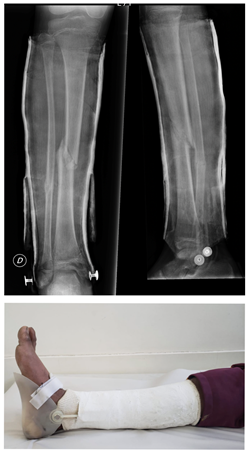

Una de las mayores fortalezas de este tratamiento es la libertad e independencia que le genera tanto al paciente y a sus cuidadores al compararla con otros tipos de tratamientos que deban mantener una inmovilización, la cual no permita el apoyo y la movilidad de las articulaciones vecinas. Este estímulo funcional precoz permite que al momento de retirar el yeso, el período de readaptación sea corto y no haya necesidad de realizar ningún tipo de rehabilitación o fisioterapia específica. Si bien las repercusiones en las actividades de la vida diaria se miden de forma subjetiva, obtuvimos un 100% de satisfacción con este método ya que los pacientes a la semana de comenzar el período funcional, estaban reintegrados a su actividad diaria por completo. Figura 3.

Tuvimos 2 pacientes que presentaron complicaciones menores, a los cuales se les rompió la cazoleta abisagrada plástica a la tercera semana del tratamiento funcional. Destacamos que en uno de los casos la misma se rompió mientras el paciente practicaba fútbol con su yeso funcional. Como ya mencionamos, un paciente presentó una angulación mayor a 5º (6º de varo) Figura 4, la misma era imperceptible clínicamente. Por lo que estamos ante una técnica segura con bajo o nulo número de complicaciones, la cual nos permite en caso de que sea necesario cambiar de tratamiento según lo requiera la situación de la lesión y el paciente. Evitando complicaciones inherentes a tratamientos quirúrgicos como son lesiones nerviosas o fisarias iatrogénicas, infección relacionada a materiales de fijación, intolerancia de implantes, entre otras 1